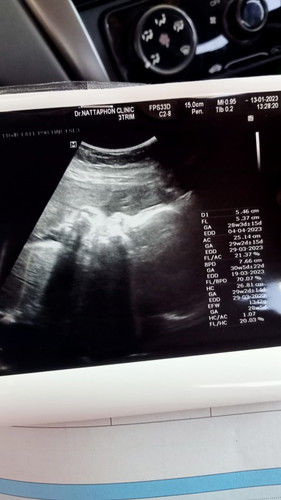

แม่ๆ น้ำหนักน้องเท่าไหร่กันแล้วคะ บ้านนี้ 28 วีค 1300 กรัม น้อยรึป่าวคะ บำรุงอะไรเพิ่มดี😁😀ช่วยแนะนำหน่อยจ้า ตอนนี้กินนมแพะอยู่ค่ะ เอามือปิดหน้าด้วย😂

ไม่น่าจะน้อยนะคะ เกณฑ์ 28วีค 1,005กรัมเองค่ะ ถ้าหมอไม่ว่าอะไรคือปกติค่ะ หมอแจ้งว่ายังไงบ้างคะแม่ // เอ็นดูจังเลยเอามือปิดหน้า น้องเขินเหรอลูก😂 ผช. หรือ ผญ. คะแม่

ลูกสาวเรา 28 วีคหนัก 1229 กรัม คุณหมอบอกไม่มากไม่น้อยเกินไปปกติดีค่ะ แม่เน้นกินโปรตีนจะได้ลงลูกนะคะ